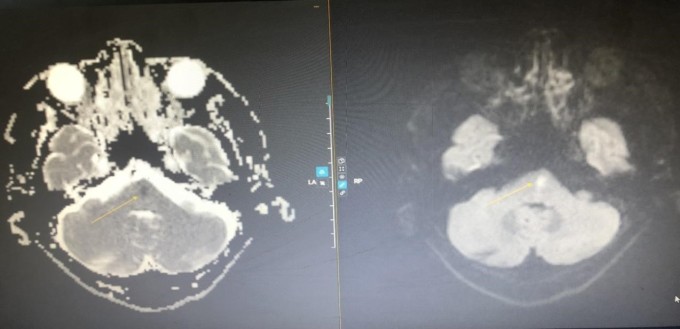

Vị trí nhồi máu não vùng thân não (trái) và sau khi được can thiệp tiêu sợi huyết gây đột quỵ qua hình ảnh MRI (phải) (Ảnh: Bệnh viện Đa khoa Tâm Anh)

Bệnh viện phát y lệnh khẩn “Code Stroke” (“báo động đỏ” cấp cứu đột quỵ), ưu tiên nhân lực, máy móc cứu người đột quỵ. Bệnh nhân được chụp cộng hưởng từ (MRI). Sau 10 phút, kết quả cho thấy nhồi máu cầu não, không có tắc mạch máu lớn nội sọ.

Theo bác sĩ Minh Đức, tổn thương của bệnh nhân nằm ở vùng thân não trọng yếu, nơi tập trung các bó sợi thần kinh đi xuống tủy sống, có hệ thống lưới đảm nhiệm chức năng thức – tỉnh của con người. Bệnh nhân có triệu chứng đột quỵ trong khoảng 4 đến 4,5 giờ, dù còn giờ “vàng” nhưng không thể chậm trễ hơn vì để càng lâu biến chứng càng nặng.